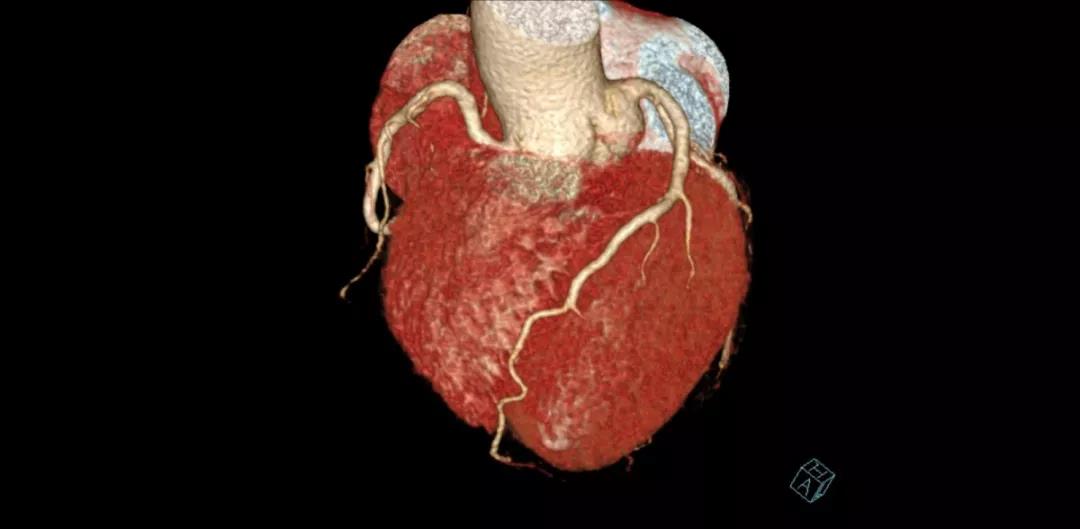

案例圖

冠狀動脈CTA